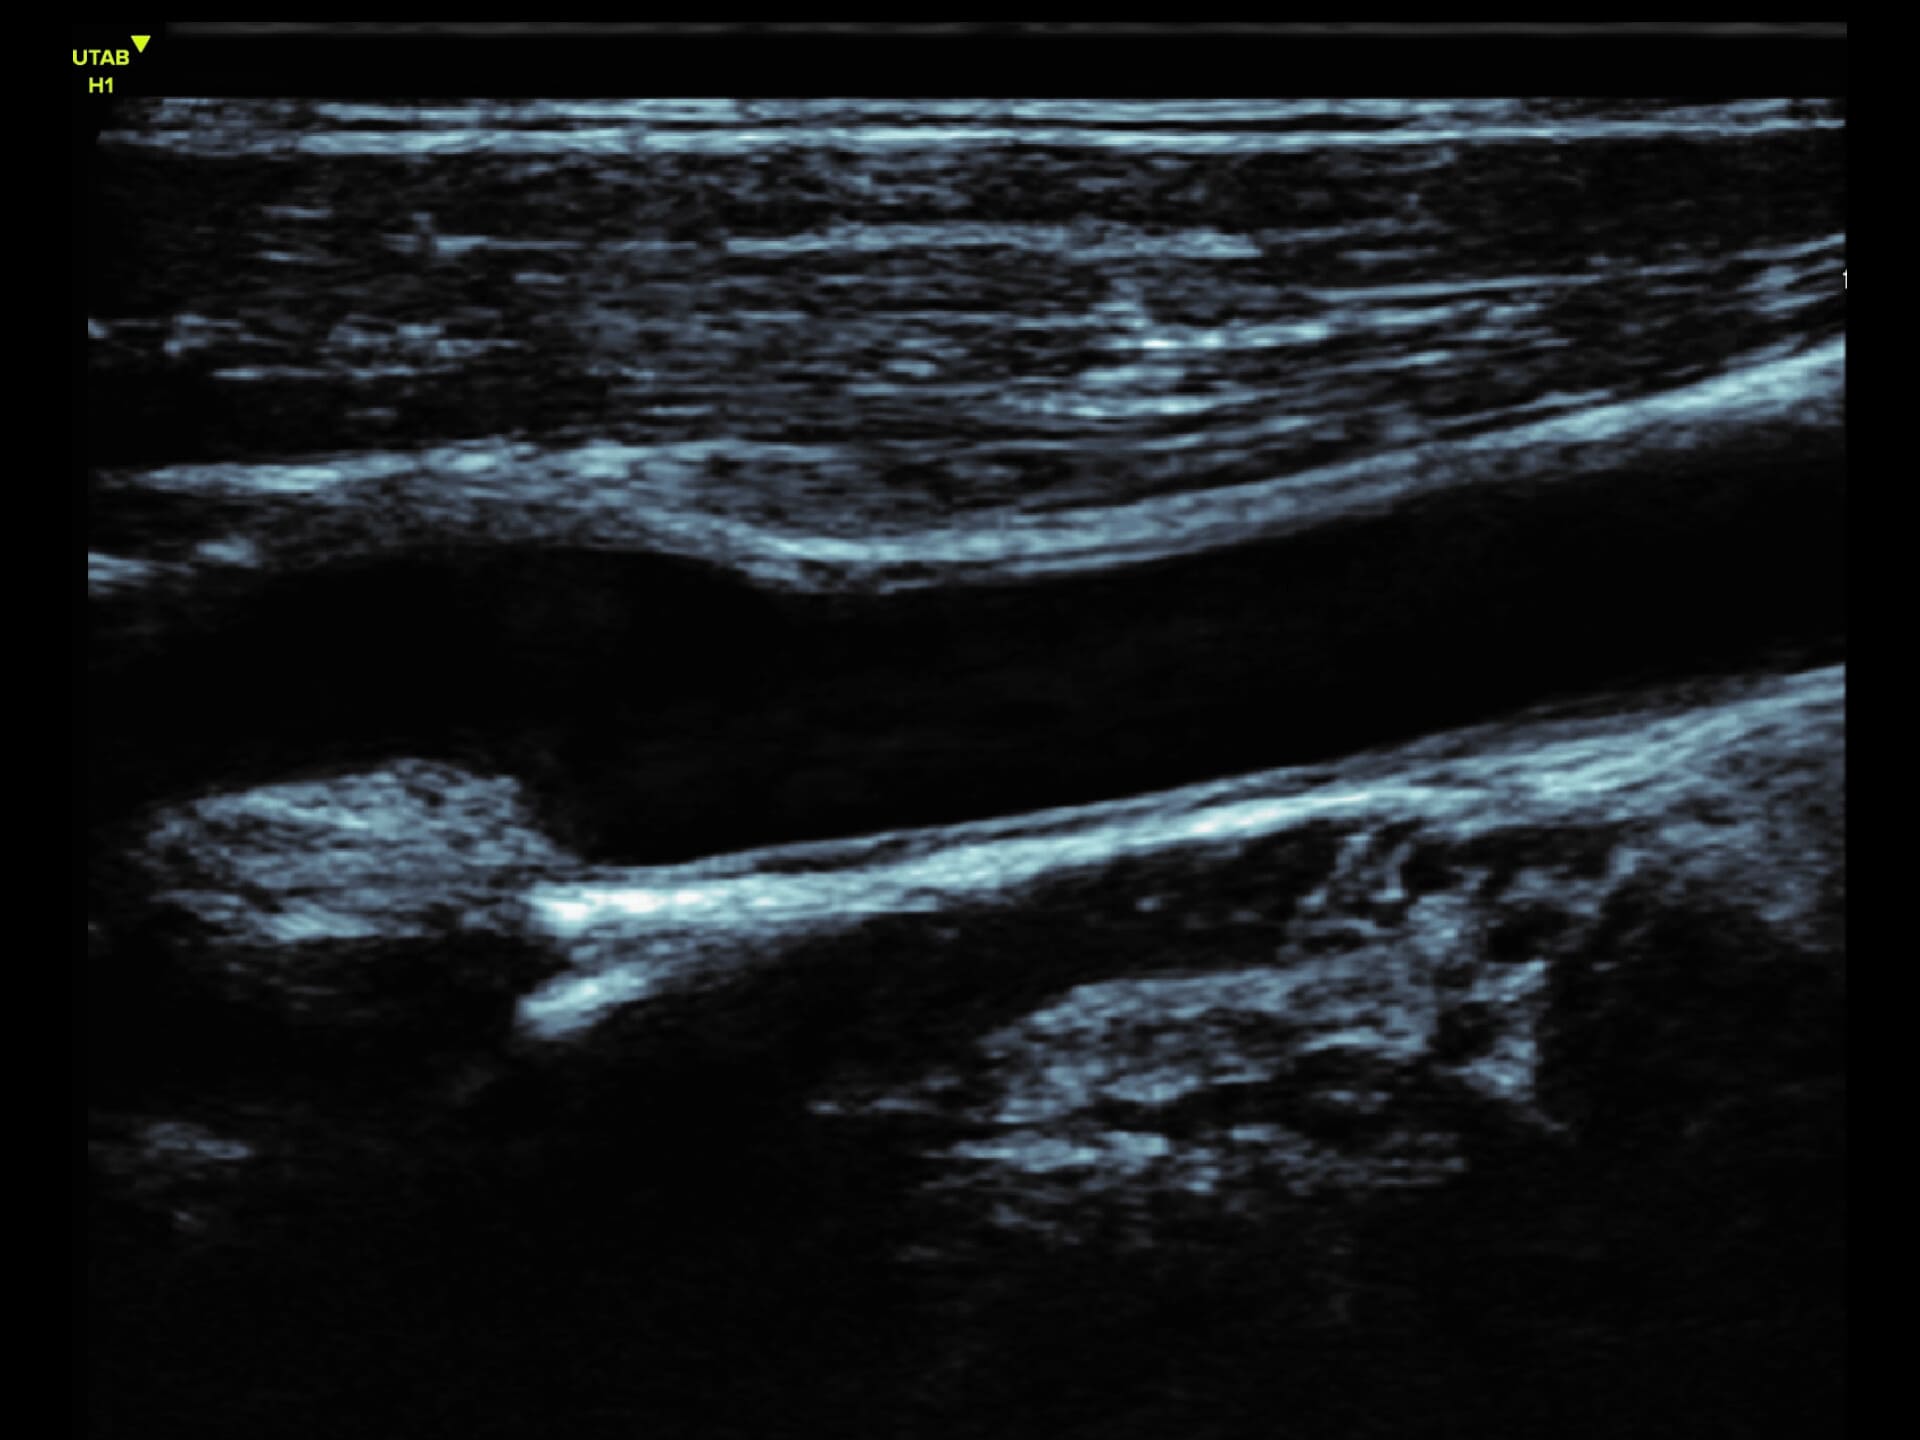

L9-2 Linear Array Probe

Precision at the Surface

Crystal-clear imaging for muscles, vessels, and soft tissues—perfect for targeted exams and real-time procedures.

The L9 – 2 is a linear array ultrasound probe featuring advanced wideband technology, which enables a broader frequency range for superior image resolution and clarity. This enhanced imaging capability makes it ideal for a range of clinical applications.

About L9-2

The L9 – 2 is a linear array ultrasound probe featuring advanced wideband technology, which enables a broader frequency range for superior image resolution and clarity.

This enhanced imaging capability makes it ideal for a range of clinical applications.

L9 - 2 Linear Array Probe

2 - 10 MHz

DLP

192 elements

Applications:

Musculoskeletal, Thyroid, Small Parts, Pediatrics, Peripheral Vascular, Breast, Obstetrics

B-mode, HI, XBeam, Speckle Reduction, Virtual Convex, M-mode, PW (Update, Duplex, Triplex, HPRF), CFM, PD

7 x 43 mm